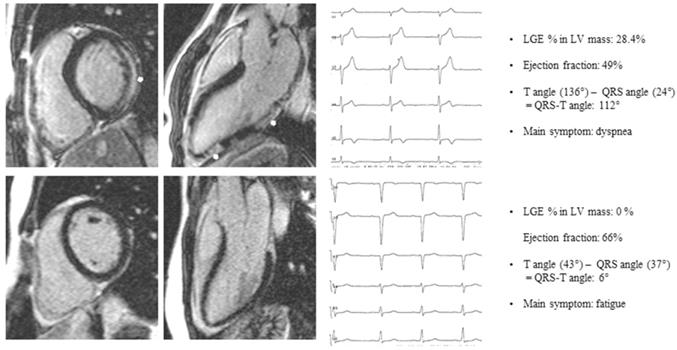

In 97 patients (23 female, mean age 47.1-18.5 years) with an ejection fraction of 55.9-10.8% mean QRS-T angle was 48-45. 78 of 97 (80%) patients showed myocarditis type LGE on contrast-enhanced CMR, 19 of 97 (20%) patients had no signs of fibrosis on LGE CMR. Clinical examples are given in Figure 1. Analysing the data we found a moderate but highly significant correlation between LGE as percentage of LVmass and the QRS-T angle of 0.559, p<0.001. In patients with LGE QRS-T angle was greater than in patients without LGE (53.95-47.5 vs. 26.2-21.2; p<0.001). As a consequence of myocardial damage or more severe disease patients with LGE had a lower ejection fraction (54.6-11.6% vs. 60.7-4.3; p=0.016).

Figure 1

Patient A: basal end-diastolic short axis and 3-chamber long axis LGE image of a patient presenting with dyspnea, subepicardial LGE (white arrows), LGE % LV mass 28.4%, Ejection fraction 49%, QRS-T angle 112°. Patient B: basal end-diastolic short axis and 3-chamber long axis LGE image of a patient presenting with fatigue, no LGE, Ejection fraction 66%, QRS-T angle 6%. LGE late gadolinium enhancement.